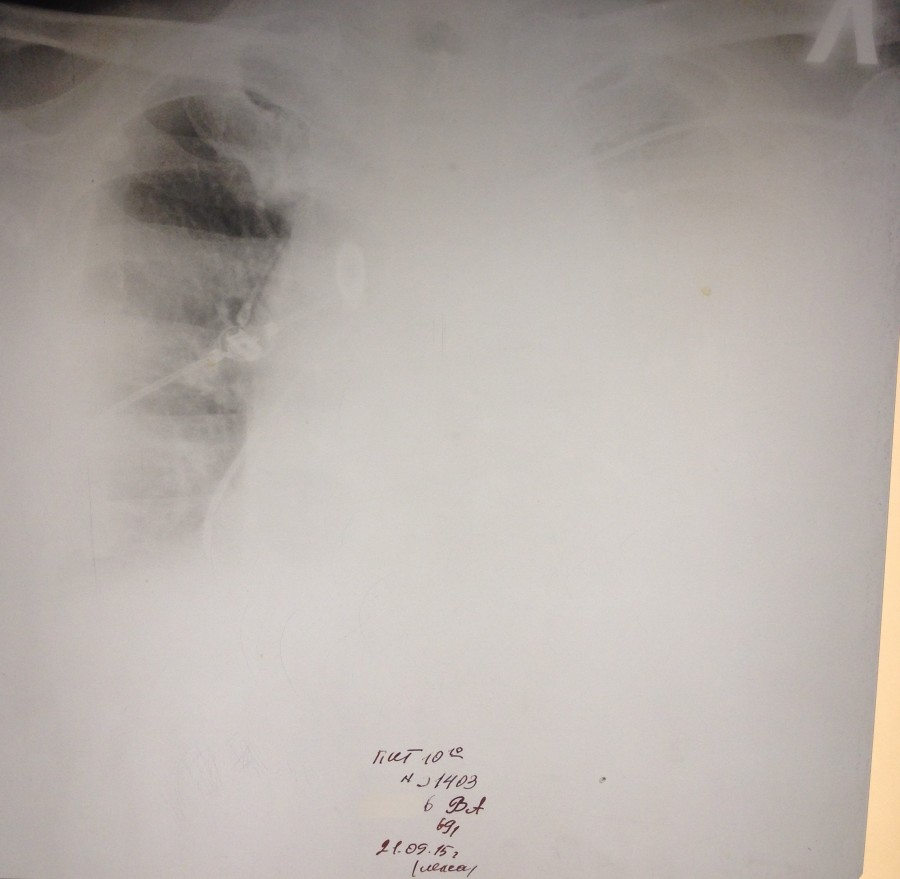

Ж 84 года. В маразме. РАА дуги и нисходящего отдела, доказана МСКТ. Поступила с болями в левом боку. На первом снимке левосторонний гемоторакс. На втором накопление жидкости до тотального уровня. На третьем после дренажа. Не оперирована. Выписана домой на 23 день госпитализации.